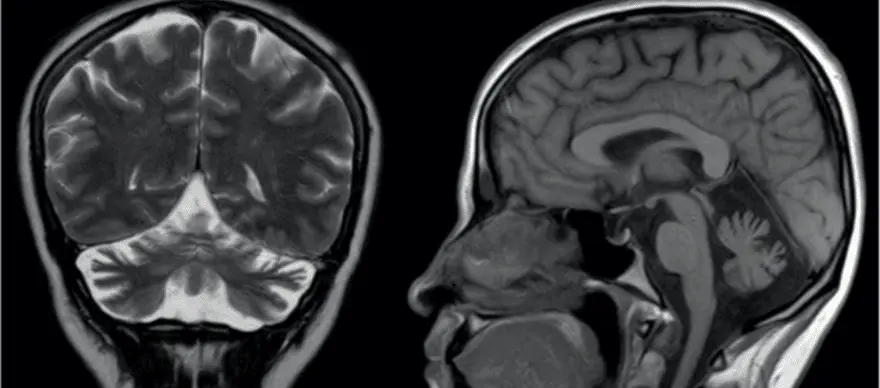

What is Spinocerebellar Ataxia Spinocerebellar Ataxia (SCA) or Spinocerebellar Degeneration is a neurodegenerative disorder that affects the proper functioning of brain-body coordination and may cause difficulties with walking and performing fine motor movements, swallowing, and weakness in muscles controlling the eye movement. Numerous conditions can cause Cerebellar and Spinocerebellar Degeneration. However, acute injuries or infections and damages affecting the parts of the brain controlling the motor movements (cerebellum) are the significant cause of Spinocerebellar Ataxia. Currently, there is no effective cure or treatment for Spinocerebellar Ataxia. However, not all ataxia types cause equally severe abnormalities. In general, treatments for most Spinocerebellar Ataxia cases involve focusing on relieving the specific symptoms and lowering the progression of ataxia. Types Of Ataxia There are several types of ataxia. Based on their symptoms and their causing factor for developing neurodegenerative conditions, researchers and doctors have classified ataxia into numerous types, some of which are given below. Knowing the types and their unique symptoms can help you and your doctors evaluate and rule out similar disease conditions and determine a proper treatment plan. Ataxia-telangiectasia: Also known as Louis-Bar Syndrome, it is a rare type of early onset inherit ataxia (passed from parents to children) that affects the immune and nervous systems of the body. The symptoms of ataxia-telangiectasia can develop at an early age, usually at 1-5 years of childhood, and its symptoms tend to get worse with time. Friedreich’s ataxia: Friedreich’s ataxia is the most common type of ataxia affecting people worldwide. Although both Friedreich’s ataxia and telangiectasia share many common symptoms and causal factors, the progression and onset period greatly differ. The symptoms of Friedreich's ataxia often appear at a much later stage of childhood (15-20 years of age). Spinocerebellar ataxia: Also known as spinocerebellar atrophy or spinocerebellar degeneration, it is an ataxia that often doesn't show signs until adulthood and its symptoms usually appear between 25 to 80 years of age. Currently, based on their unique genetic abnormalities and pattern of inheritance (passing from parents to children), spinocerebellar ataxias are classified into 36 different types (SCA1 to SCA36). Further, based on their distant characteristics and association with defective genes, the 36 different types of SCA are grouped into the following subtypes: Subtypes of spinocerebellar ataxia Autosomal dominant cerebellar ataxia type I - includes syndromes like SCA1-SCA4, SCA8, SCA10, SCA12-SCA23, SCA25, SCA27, and SCA28. Autosomal dominant cerebellar ataxia type II - includes SCA7. Autosomal dominant cerebellar ataxia type III - includes SCA5, SCA6, SCA11, SCA26, SCA29, SCA30, and SCA 31. Idiopathic late-onset cerebellar ataxia (ILOCA): Also known as Multiple System Atrophy (MSA), it refers to conditions for which the exact cause and medical reason for why a person develops ataxia are not clearly understood and identified. Early Symptoms To Watch Out for Spinocerebellar Ataxia Spinocerebellar Ataxia Symptoms depend largely on the severity and stage of the condition. Some general symptoms of ataxia include Poor/decreasing control in mind-muscle coordination Slurred speech Difficulties in performing day-to-day fine motor activities Headache Dizziness Visual impairment Involuntary rapid eye movements Unsteady/difficulties in walking movements Loss of sensation Possible Causes Behind Spinocerebellar Ataxia Spinocerebellar ataxia happens largely due to defect or damage to the parts of the brain (cerebellum) that controls muscle coordination. Further, defects or mutations in genes responsible for the proper functioning of the nerve cells in the brain can also trigger and lead to spinocerebellar ataxia. Based on the nature of the causing factors, researchers and doctors have categorized ataxia into three major groups, namely, Acquired causes: This includes external factors that cause ataxia. Some potential external causes include Head injury/ trauma Adverse side effects of certain medications Thyroid problems Exposure to infection Cancer or other underactive illness affecting brain function Hereditary causes: The hereditary causes include defects/mutations in genes that lead to abnormal functioning of nerve cells in the brain. Based on their mode of inheritance (passage from parents to children) and certain other characteristics, they are mainly classified into two types, namely Autosomal Recessive: The affected individual gets defective genes from both the parents (mother and father). Ataxia-telangiectasia and Friedreich's ataxia are generally inherited in this way. Autosomal Dominant: The presence of a single copy of a defective gene (either from the mother or father) is enough to cause an ataxia condition. Many cases of spinocerebellar ataxia are inherited in this way. Degenerative causes: Age-related wear and tear on muscles and spinal discs, presence of other underactive illnesses such as high blood pressure, and internal haemorrhage are included under degenerative causes. How Is Spinocerebellar Ataxia Diagnosed? The diagnosis of spinocerebellar ataxia primarily targets evaluating the regions of the affected/ damaged areas of the cerebellum and analysing the type of genetic defect present in the individuals. Some standard diagnostic techniques used include Magnetic Resonance Imaging (MRI) scan of the brain Non-Invasive Computed Tomography (CT) scan to analyse the shrinkage in the brain Blood test to determine other associated illnesses Modern genetic testing to confirm hereditary related gene defects The DNA tests for Spinocerebellar Ataxia [SCA tests] further help to diagnose and classify the ataxia into various types. What Can Put You At a Risk Of Developing Spinocerebellar Ataxia? Many health conditions and factors can put you at risk of developing ataxia. Some possible risk factors of ataxia include Exposure to viral infections such as coxsackie virus, chicken pox, Epstein-Barr, coronavirus, or Human immune virus (HIV) Bacterial infections such as Lyme disease Vitamin and nutrient deficiencies Alcoholism Overuse of certain medications Presence of underlying blood clots, haemorrhage, or obstruction of a blood vessel What Are The Treatment Options Available For Spinocerebellar Ataxia? Currently, there is no effective or specific treatment for spinocerebellar ataxia (SCA). However, in general, the treatment for SCA usually focuses on alleviating the signs and progression of the condition. Some common treatments and strategies for managing the signs of SCA involve Physiotherapy to improve balance and mobility Speech therapy to improve slurred speech and swallowing problems Medical devices to assist in performing fine motor skills and self-care activities Medication to relieve symptoms such as tremors, depression, stiffness, muscle pain and sleep disorders What Is The Prognosis And Outlook For Individuals With Spinocerebellar Ataxia? Medical advancements and modern technologies are not adequately successful in preventing spinocerebellar ataxia. However, accurate diagnostic technologies are available to identify the defective genes in SCA patients. The next step is to correct those defects using gene therapy technology. The use of gene therapy technology is still in its infancy. However, the future holds promising results and outlook in treating SCA. CTA: Getting a Spinocerebellar Ataxia Type 12 (SCA12) DNA test along with other screening methods can increase the odds of early detection. The early detection of spinocerebellar ataxia may lead to better management, positive outcomes and longer survival in the patient.